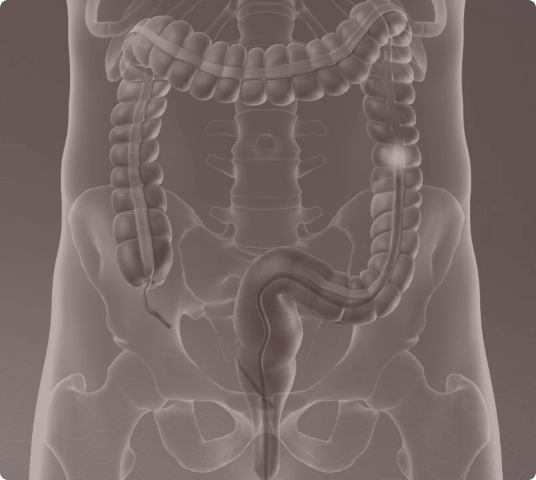

Virtual colonoscopies have emerged as a great alternative to conventional colonoscopies. Not only are they more convenient, but they are less invasive, more comprehensive, and have fewer complications. Our virtual colonoscopy images are generated by a CT scan of your abdomen and pelvis. These images can show polyps and other abnormalities inside your colon and rectum.

Similar to a conventional colonoscopy, a small tube will be inserted into the rectum. This tube is used to pump CO2 into the colon. Because the tube is shorter with a virtual colonoscopy, there is minor discomfort during and following the procedure, which is why there is no need for pain medication. When pumping CO2 into the colon, as is done with both procedures, there is a small risk of tearing or rupturing the colon. However, it is believed that the risk is reduced with the virtual procedure because we limit/monitor each individual’s pressure during the exam..

Preparing for a virtual colonoscopy is similar to preparing for a conventional colonoscopy. You’ll be placed on a clear liquids-only diet for 1 or 2 days before the procedure; this will include clear broth, water, or an electrolyte solution. In order to get clear images of the colon, it must be empty. You’ll be given a laxative the day before the procedure. A detailed preparation plan will be provided prior to your appointment.